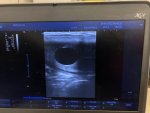

My maiden mare on day 353 ??? I only have a week of leave left and she’s no closer to look at than she was two weeks ago!!! Small amount of udder development that goes down by tea time but no relaxation at the back.